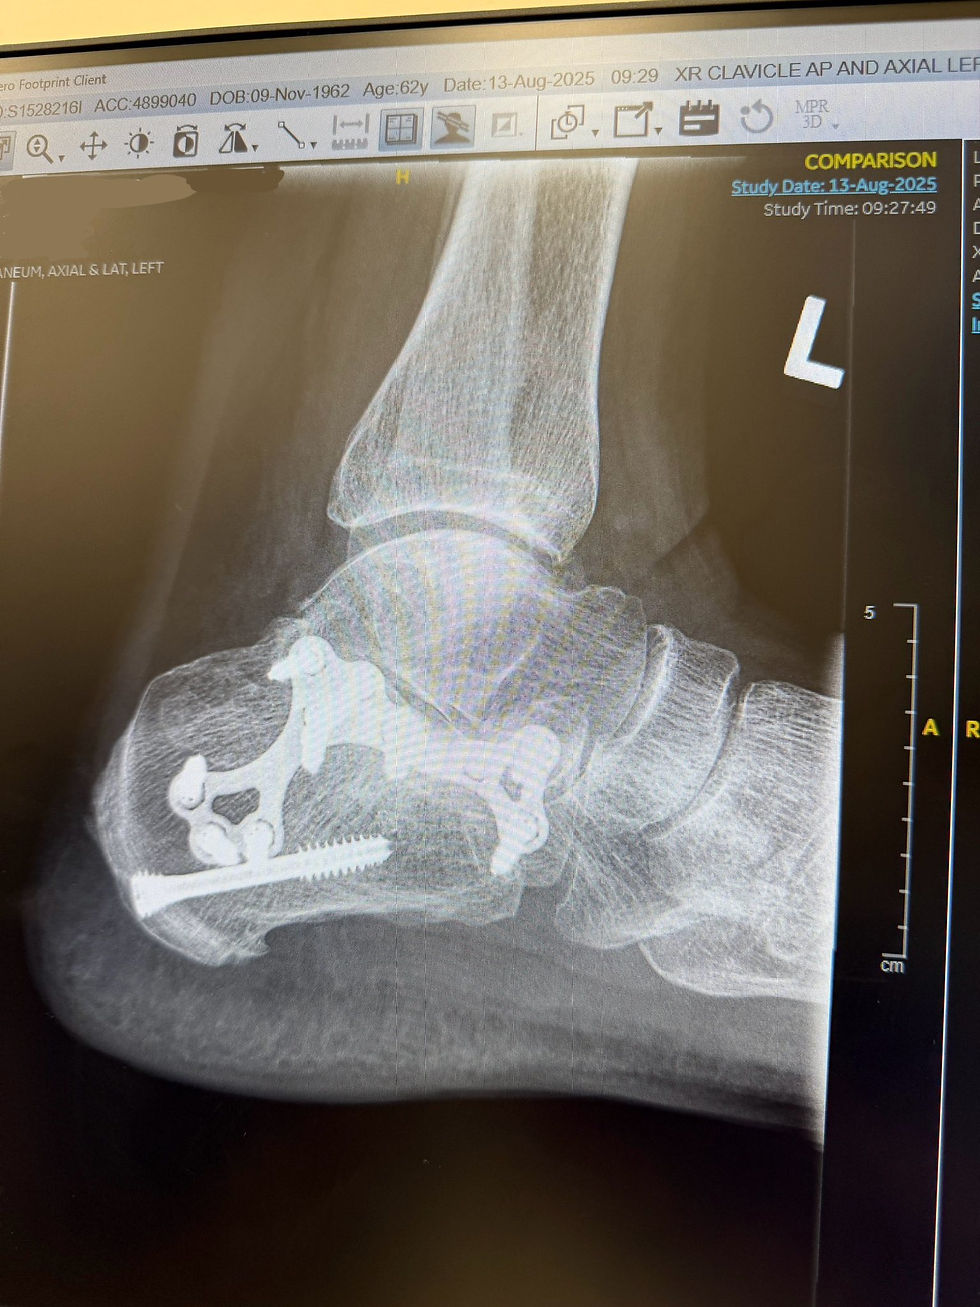

Today, that chapter closes. My orthopaedic has officially released me. My injury is fully healed, and there’s no need for any more reviews. It’s a moment I’ve been waiting for, and I’m deeply grateful to everyone who played a part in getting me here.